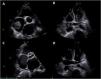

The patient was admitted to the intensive care unit (ICU) and started anticoagulation with unfractionated heparin (UFH). Despite five days with an activated partial thromboplastin time (aPTT) in the target range (60-80 s), the patient's clinical condition deteriorated and venous ultrasonography revealed extensive bilateral popliteal vein thrombosis. Repeat TTE showed severe deterioration of right ventricular systolic function and persistence of the right atrial masses with similar dimensions, together with mobile thrombi on the coronary sinus and the right pulmonary artery (Figure 2A and B). Urgent surgical thrombectomy was considered, but after consultation with the cardiac surgery team it was decided that the risk outweighed the benefit at that particular clinical juncture. After exhaustive discussion and literature review, it was decided to apply an ultra-slow low-dose thrombolysis protocol with a solution of 50 mg alteplase diluted in 100 mg isotonic saline at a rate of 1 mg per hour, without alteplase bolus, via a peripheral catheter placed in the right external jugular vein. The UFH infusion was maintained to a target aPTT of 50 s. After 24 hours of alteplase perfusion there was a moderate decrease in the atrial masses, as reported by TTE. The treatment was maintained for a further 24 hours and TTE was repeated, revealing a significant reduction in the right atrial masses with resolution of the coronary sinus and right pulmonary artery thrombi. Alteplase infusion was discontinued but the patient continued under treatment with UFH to a target aPTT of 60-80 s. Hemoglobin and platelet count remained stable during thrombolysis and there were no major bleeding complications. The patient was discharged from the ICU and started anticoagulation with warfarin, bridging with low molecular weight heparin. Seven days after alteplase discontinuation there was complete resolution of the intracardiac thrombi and 14 days later the patient was discharged from hospital under warfarin therapy (Figure 2C and D).

Transthoracic echocardiography four days after admission to the intensive care unit, showing persistence of the right atrial masses with similar dimensions (A) together with mobile thrombi on the coronary sinus (B) and the right pulmonary artery. Seven days after thrombolytic treatment there was complete resolution of the right atrial masses and thrombi on the coronary sinus and right pulmonary artery (C and D).